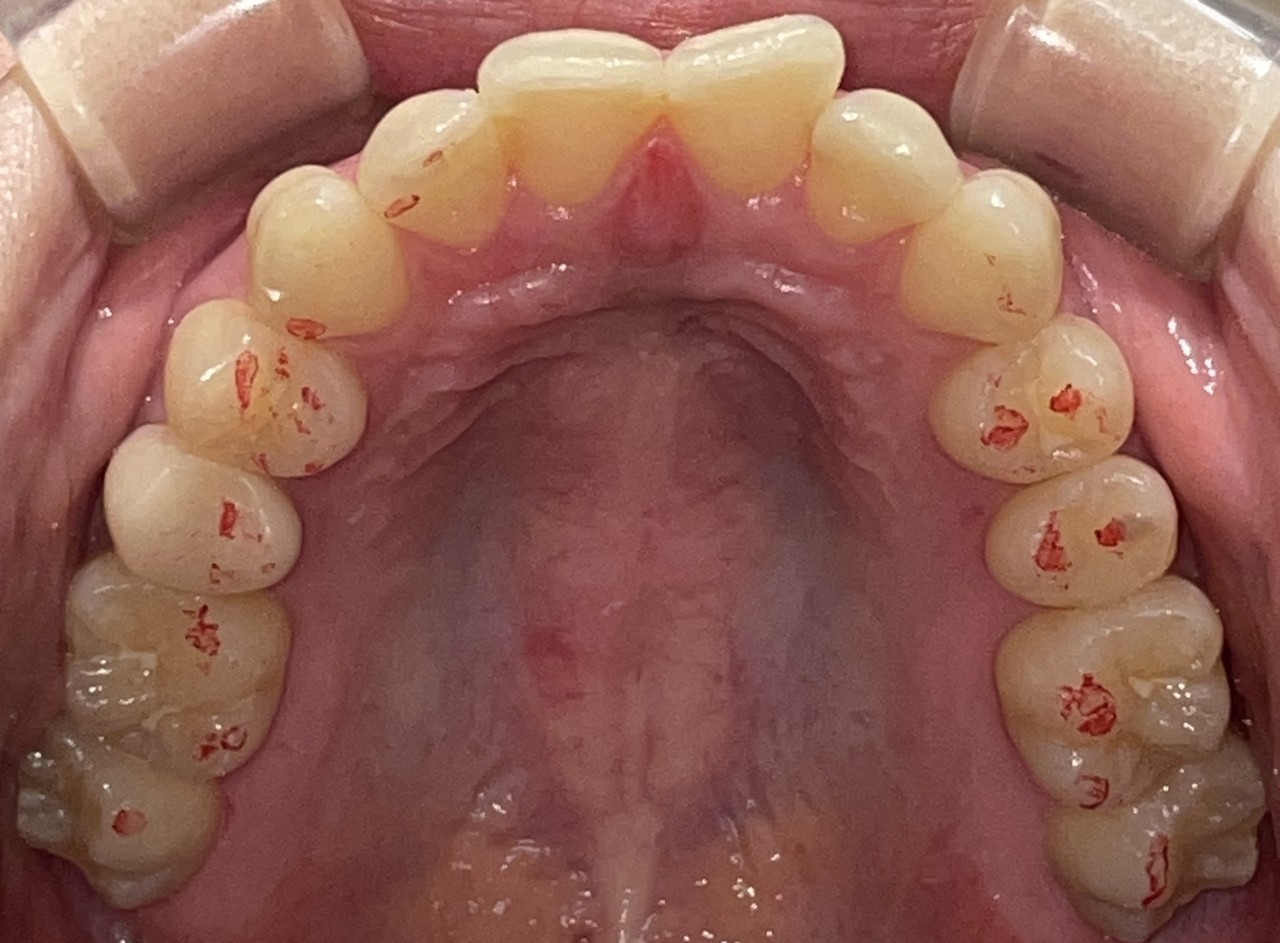

Before

After

矯正の種類 / invisalign GO

年齢・性別 / 40代女性

主訴  /  上下の叢生、開咬、オーバージェット

治療期間 / 12ヶ月

費用 / 簡易検査 5,000円(税別) 精密検査 30,000円(税別)

両額マウスピース 450,000円(税別) 両額リテイナー料 40,000円(税別)

※マウスピース交換時別途調節料5,000円(税別)

副作用 / 口内炎・歯の移動に伴う痛み・知覚過敏 ※数日で収まる場合が多いです

リスク / 後戻り防止の為、夜のみマウスピースで保定を指示